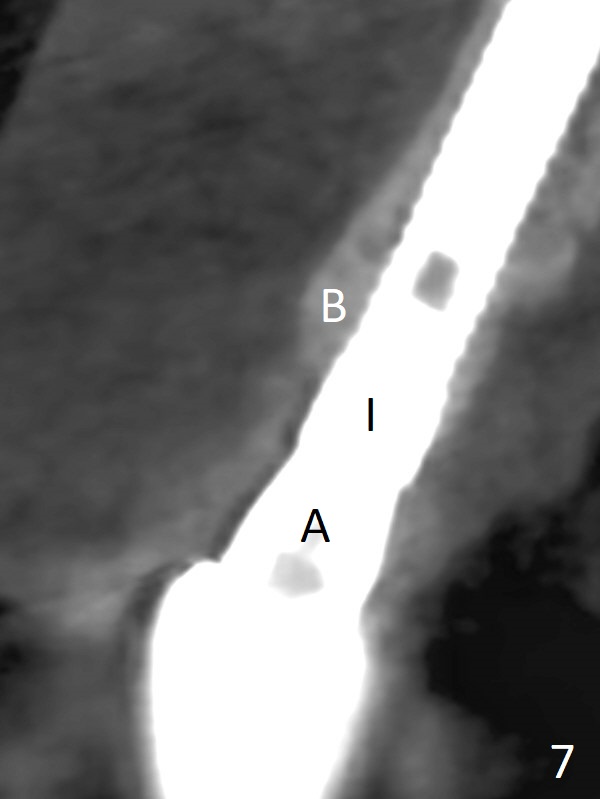

The patient returns because of purulent exudate from the buccal fistula (Fig.1 *) 1 year 9 months postop (1 year 3 months post cementation). Preop CT shows buccal thread exposure (Fig.2 arrowheads). To prevent postop gingival recession, a semilunar incision is made between the fistula and the gingival margin (Fig.3). After removal of granulation tissue (Fig.4), allograft in sticky bone form is packed (Fig.5). Following placement of PRF membrane and 6-month collagen membrane, the wound is closed (Fig.6). Since the implant (Fig.7 I) thread exposure is within bone (B) boundary (Fig.8 red dashed line), bone graft with PRF should be able to take care of periimplantitis (A: abutment). To prevent periimplantitis in similar situation, the immediate implant should be placed deep (not necessarily long, 18 mm) and narrower (3.5 mm instead of 3.8 mm). The defective buccal plate should be repaired with sticky bone and collagen membrane with incision if necessary. The wound does not dehisce 1 week postop (Fig.9) or 3 weeks postop (Fig.10, immediately post suture removal). Although bone graft seems to stay in place 6 months postop (Fig.11,12), the patient complains of bone graft expulsion sometimes. The buccal gingiva has deficiency (Fig.13). To fix it, make a remote incision (Fig.14 black line) and dissect before gingiva graft (Fig.15 dashed line). After removal of crown/abutment, the sinus track and implant surface are treated with Waterlase. A shorter cuff abutment is placed (4.5x5(4 to 3) mm) with a new provisional. The patient feels better with reduced sinus track 2 weeks postop (Fig.16).